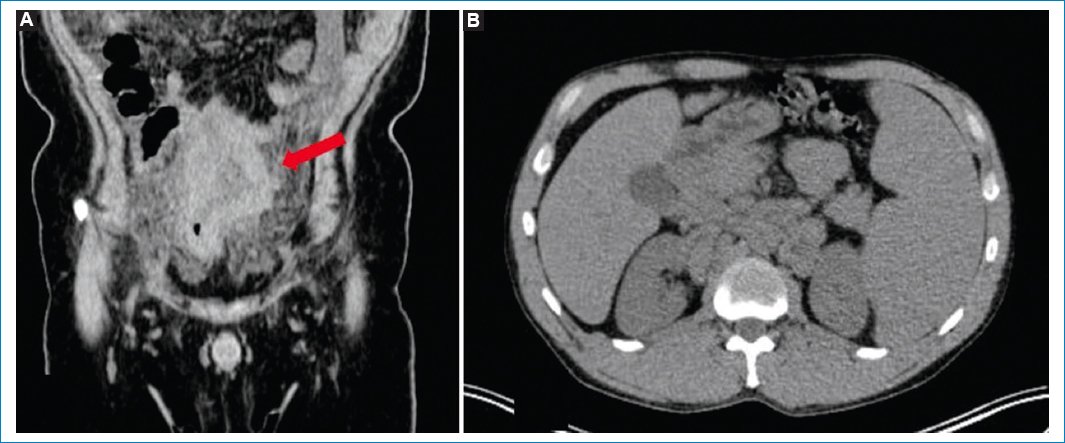

Existen algunos hallazgos asociados a los mencionados que deben inclinar la sospecha diagnóstica hacia la LP, como la presencia de adenomegalias múltiples y en diferentes niveles, nódulos peritoneales más grandes que en la carcinomatosis (en general masas), compromiso de la raíz del mesenterio y del intestino delgado, y esplenomegalia11,2931 (Figs. 2 y 3).

Figura 2. TC sin contraste endovenoso en un caso de LP, con hallazgos que respaldan la sospecha del diagnóstico. Nótense las adenomegalias retroperitoneales y pelvianas (flecha en A), los nódulos peritoneales múltiples y el grosero engrosamiento peritoneal (B).

Figura 3. TC sin contraste endovenoso en un caso de LP, con hallazgos que apoyan la sospecha del diagnóstico. Compromiso del intestino delgado evidente en la imagen coronal (flecha en A) y esplenomegalia asociada (B).